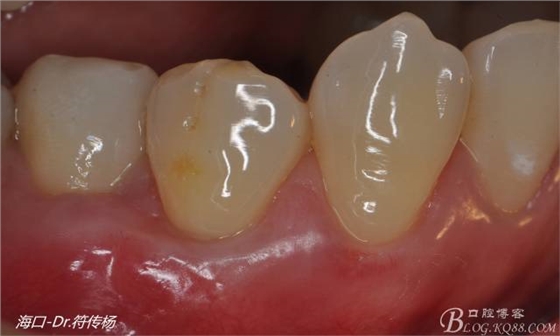

術(shù)后兩月